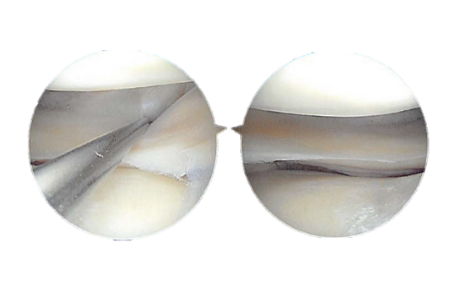

Figure 2.2. Intraoperative Arthroscopy Images

Figure 2.3 Arthroscopic view tear of the lateral meniscus posterior horn

Debridement of the cartilage was performed to remove the loose edges. Grade 2 to grade 3 OA lesions were also found on the trochlea, where debridement of the cartilage was performed. The chondroplasty was performed to remove the free edges.

The medial and lateral gutters were examined. Here was no loose body. The scope was changed from the lateral to medial portal and further chondroplasty of the patellofemoral joint, as performed. The medial meniscus was examined and found to be stable.